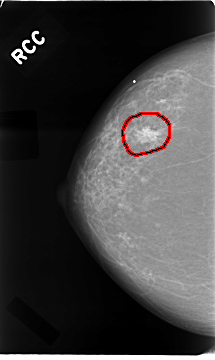

C_0016_1.RIGHT_CC

FILE: C_0016_1.RIGHT_CC.OVERLAY

TOTAL_ABNORMALITIES 1

ABNORMALITY 1

LESION_TYPE MASS SHAPE IRREGULAR MARGINS SPICULATED

ASSESSMENT 5

SUBTLETY 5

PATHOLOGY MALIGNANT

TOTAL_OUTLINES 1

BOUNDARY